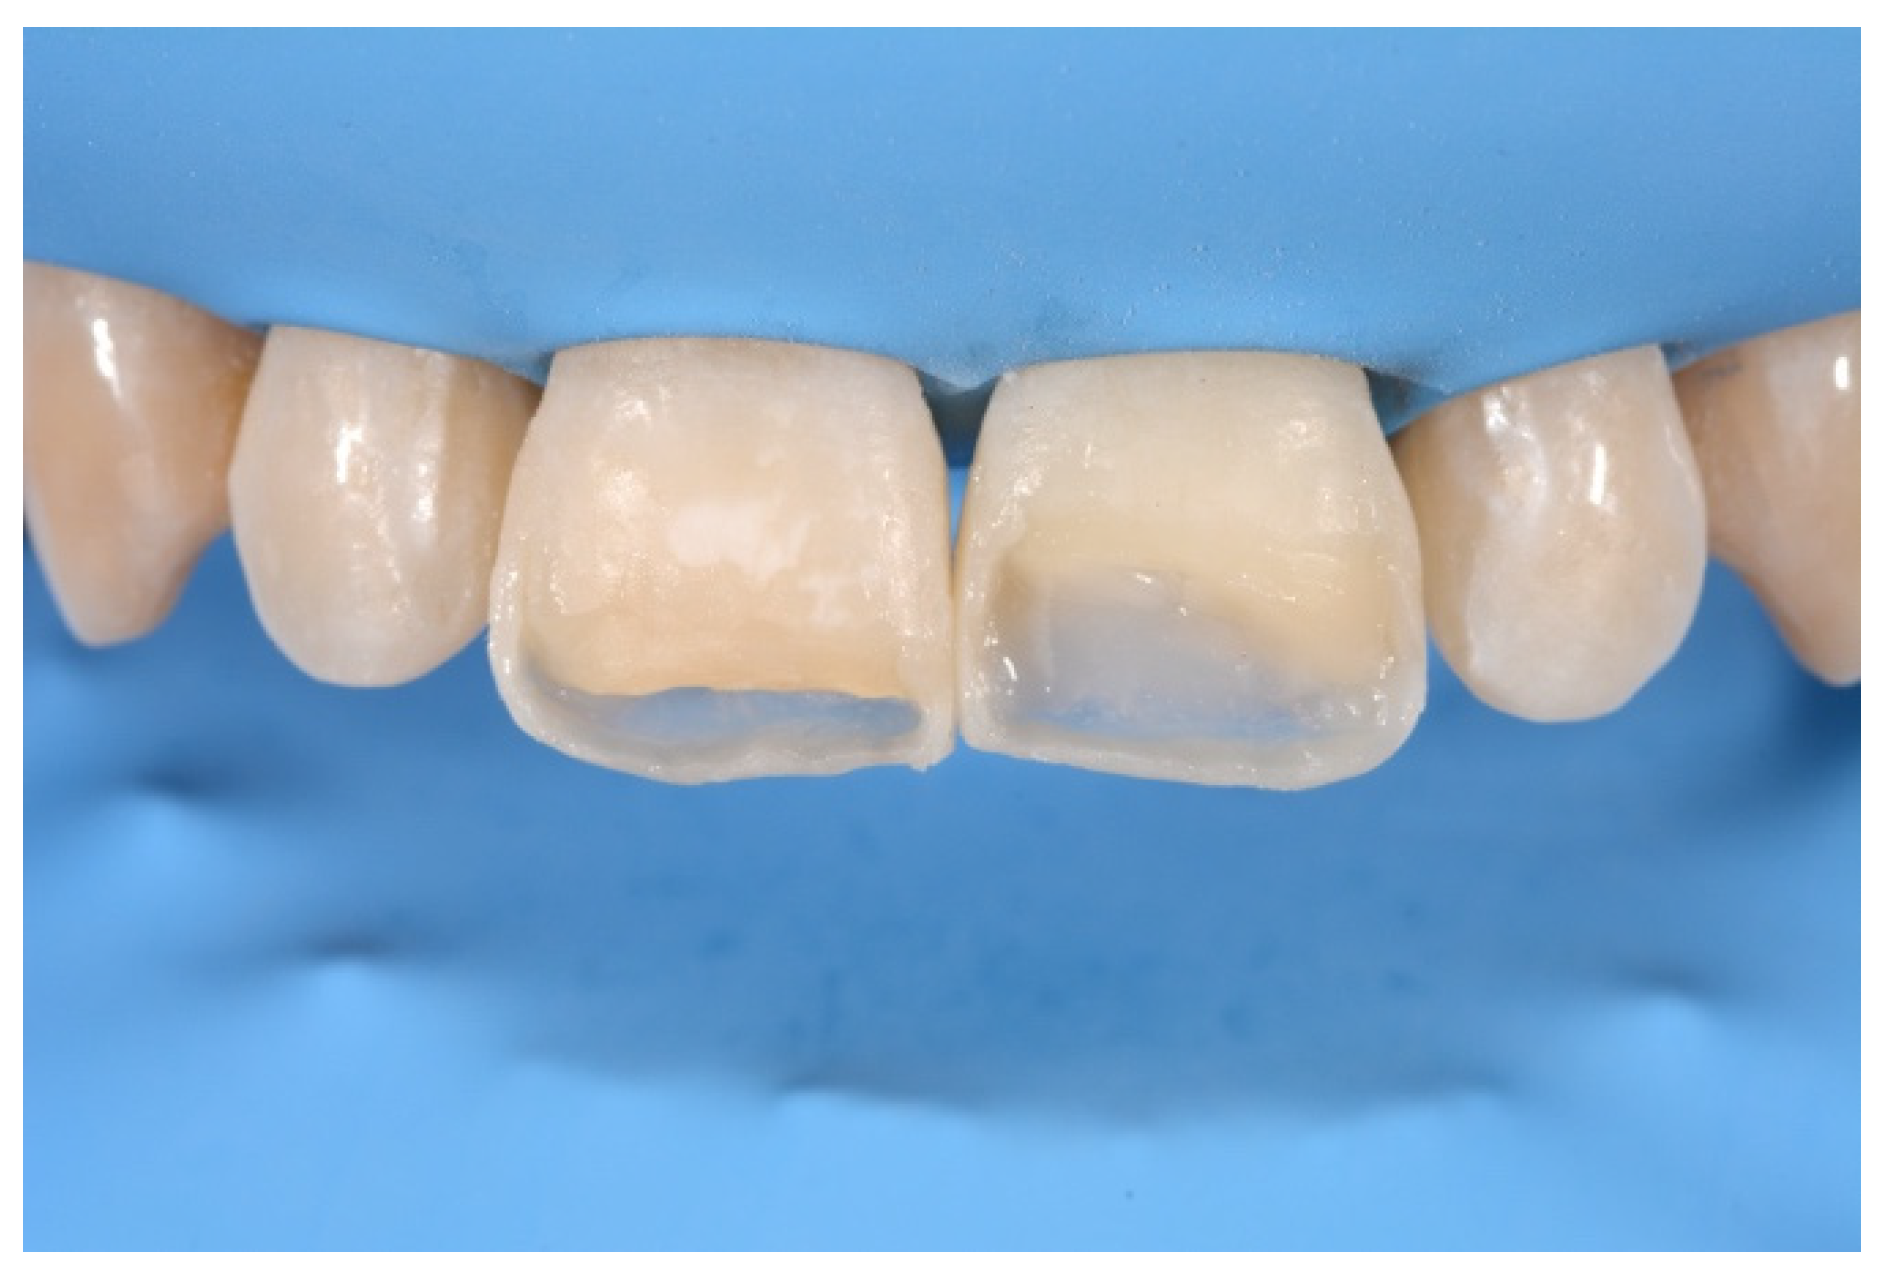

2. Case Presentation

- Molding palatal wall and incisal margin;

- Building interproximal walls with matrices;

- Layering free-hand buccal surface.